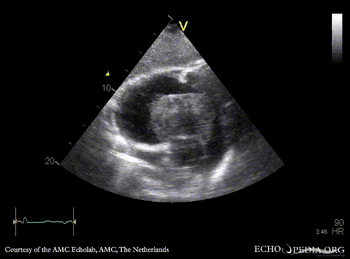

Case 152